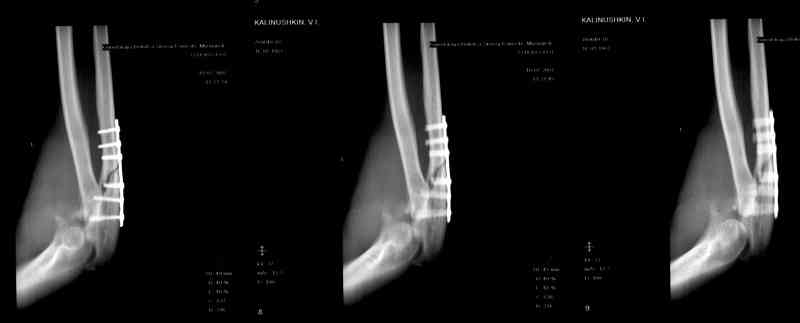

[Ortho] Несросшийся перелом локтевой кости, подвывих предплечья кзади.Перелом венечного отростка. Состояние после резекции головки лучевой. Травма 4 мес. назад.

Больной наблюдался в поликлинике,к нам попал

через 3 мес. Отмечается контрактура локтевого сустава, сгибание/разгибание 30/0/0.

МРТ у нас нет, сделаны томограммы.